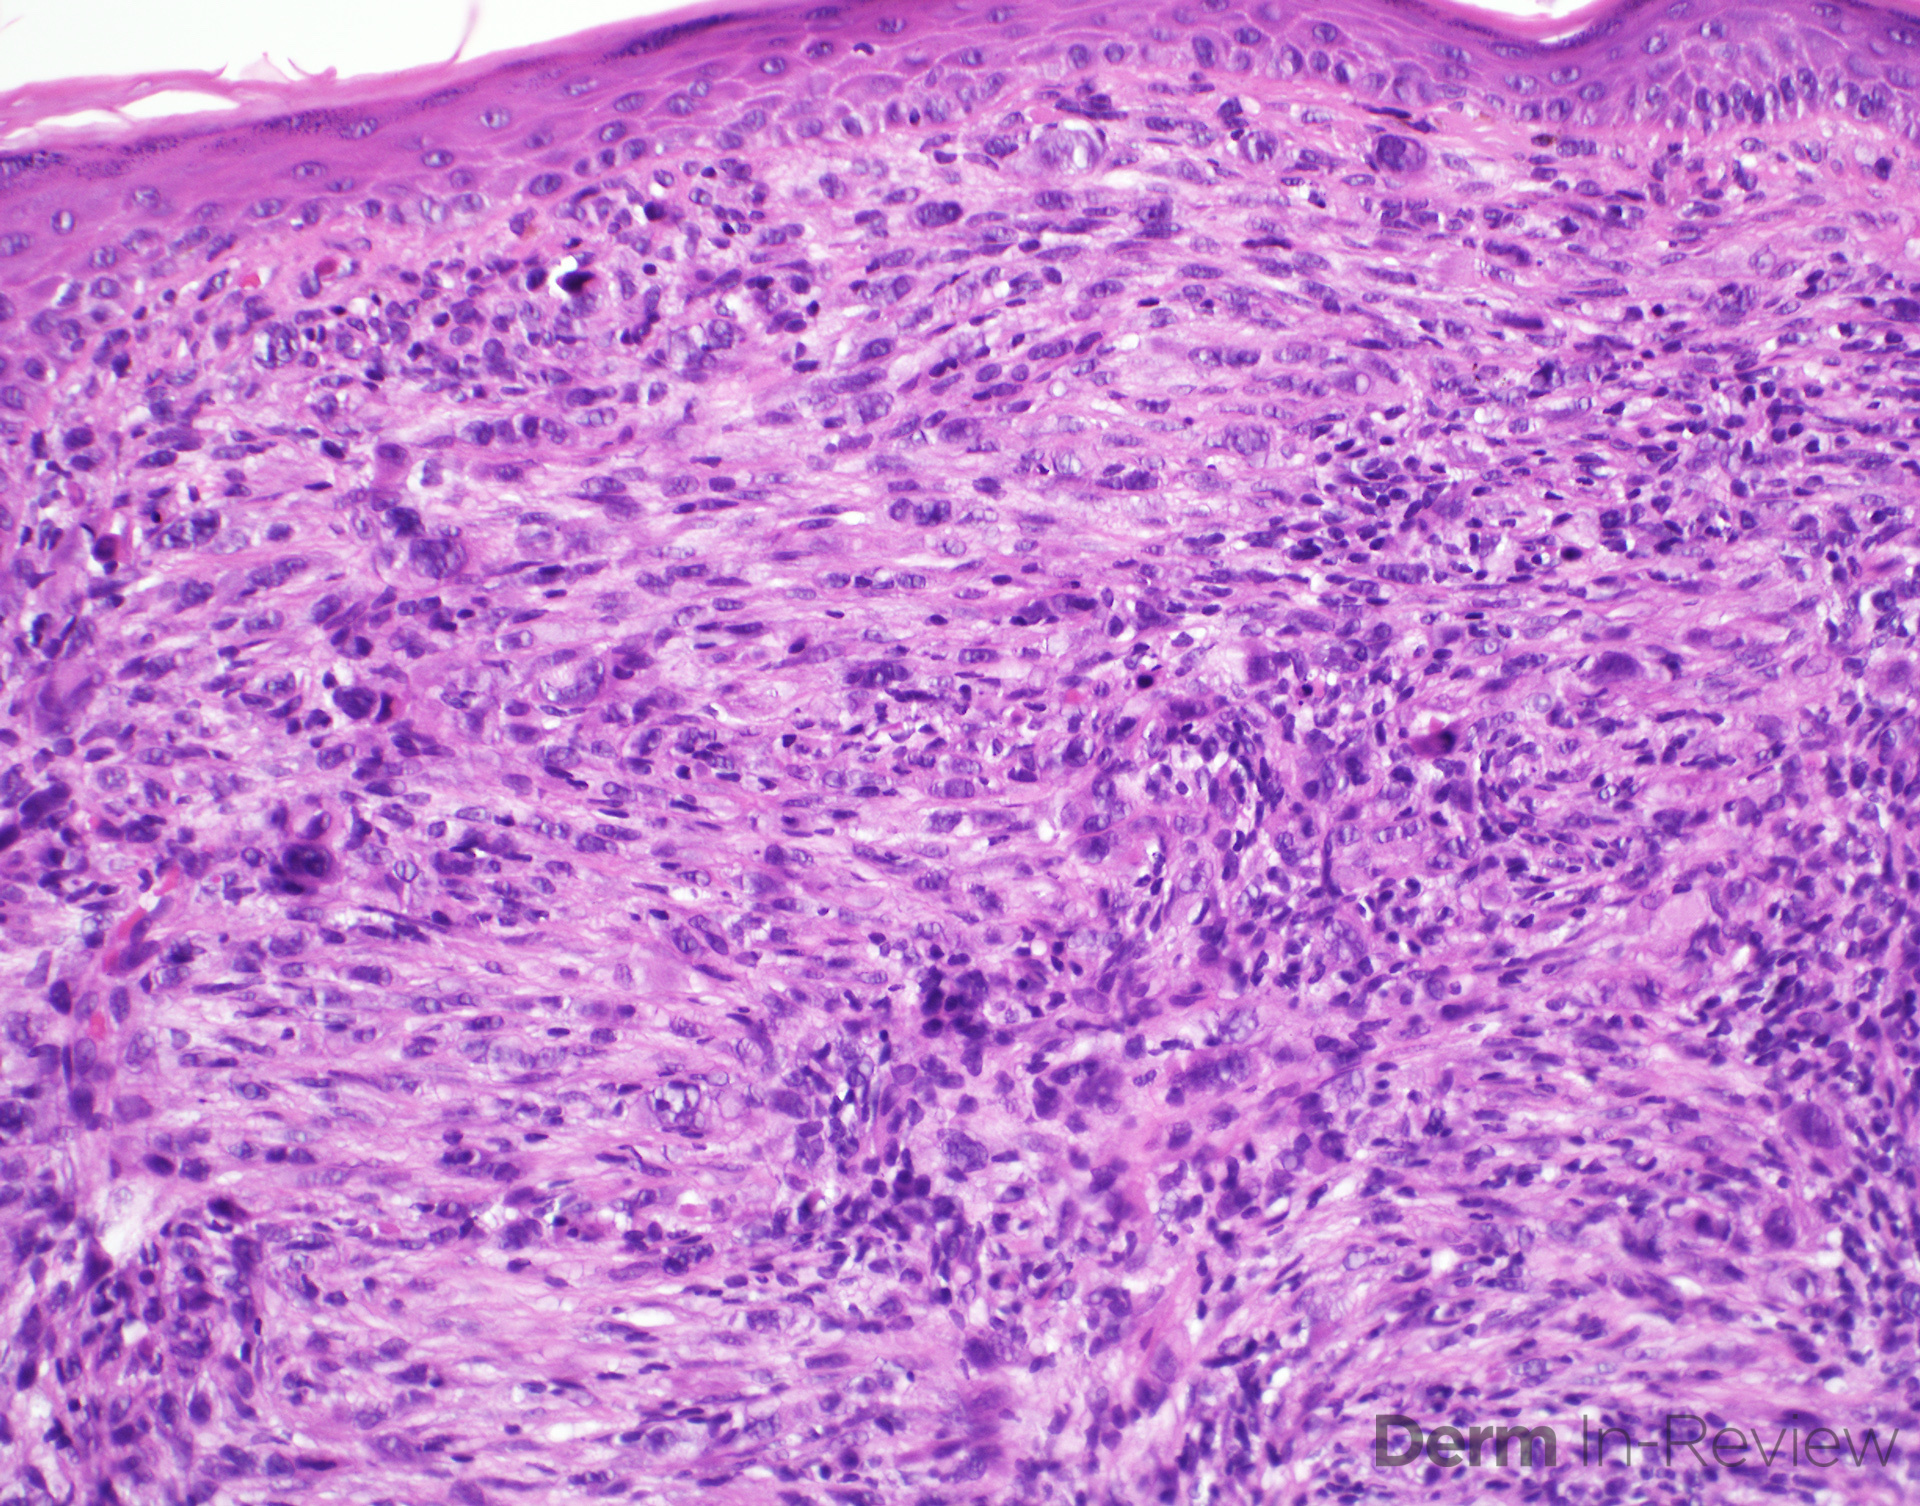

Spindle Cell Carcinoma Uptodate. spitz nevus (or spitz tumor) is an uncommon melanocytic lesion composed of large epithelioid and/or spindled cells. Gastrointestinal stromal tumors (gists) are rare mesenchymal neoplasms of the gastrointestinal tract. metastatic soft tissue sarcoma (sts) is a rare cancer that spreads to other parts of the body from the original. atypical fibroxanthoma (afx) is a rare, spindle cell skin cancer that usually affects the head or neck. the most common spindle cell lesion presenting along the uadt mucosa is spindle cell carcinoma (spcc),. although ectodermal in origin, malignant tumors affecting peripheral nerves are included because of similarities in. dermatofibroma is a common benign skin lesion due to spindle cell proliferation in the dermis. there is limited evidence for the treatment of sarcomatoid lung carcinoma, especially spindle cell. spindle cell carcinoma (spcc) consisting of variable proportions of a malignant spindle cell component and a. a comprehensive review of the histopathologic features and classification of lung cancers, based on the 2021 who. there is limited evidence for the treatment of sarcomatoid lung carcinoma, especially spindle cell. spindle cell carcinomas (spcc) of the head and neck are a rare variant of the squamous cell carcinoma. soft tissue sarcomas (sts) are a heterogeneous group of rare tumors that arise from mesenchymal cells, such as. a comprehensive overview of the pathology of head and neck tumors, with emphasis on squamous cell carcinoma. Epidemiology, pathogenesis, clinical features, and diagnosis

Spindle Cell Carcinoma Uptodate Esophageal spindle cell squamous cell carcinoma (escscc) is a distinct subtype of esophageal carcinoma. Esophageal spindle cell squamous cell carcinoma (escscc) is a distinct subtype of esophageal carcinoma. a comprehensive review of the histopathologic features and classification of lung cancers, based on the 2021 who. Approaches combining chemotherapy and radiation therapy although ectodermal in origin, malignant tumors affecting peripheral nerves are included because of similarities in. the most common spindle cell lesion presenting along the uadt mucosa is spindle cell carcinoma (spcc),. atypical fibroxanthoma (afx) is a rare, spindle cell skin cancer that usually affects the head or neck. spindle cell carcinoma (spcc) consisting of variable proportions of a malignant spindle cell component and a. there is limited evidence for the treatment of sarcomatoid lung carcinoma, especially spindle cell. spitz nevus (or spitz tumor) is an uncommon melanocytic lesion composed of large epithelioid and/or spindled cells. locally advanced squamous cell carcinoma of the head and neck: Gastrointestinal stromal tumors (gists) are rare mesenchymal neoplasms of the gastrointestinal tract. spindle cell carcinomas (spcc) of the head and neck are a rare variant of the squamous cell carcinoma. dermatofibroma is a common benign skin lesion due to spindle cell proliferation in the dermis. metastatic soft tissue sarcoma (sts) is a rare cancer that spreads to other parts of the body from the original. cutaneous squamous cell carcinoma (cscc) is a common cancer arising from malignant proliferation of the.